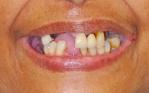

Wanda

Replacement of all upper teeth with implant supported ceramic bridgework, and implant crowns to replace the missing lower teeth.

Before